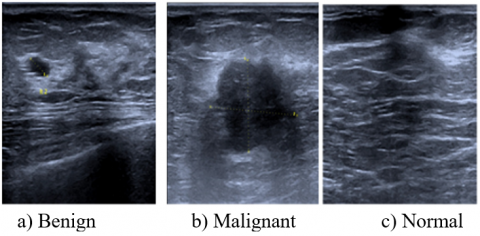

Real data of breast ultrasound images were collected from the Breast Cancer Early Detection Clinic in Imam Al-Sadiq General Teaching Hospital in Babylon, Iraq, using a device called the GE Voluson S8. The real dataset is composed of 1059 breast ultrasound images from 235 patients (723 benign, 132 malignant, and 204 normal) were selected at random from the general community to participate in this study after giving their informed consent in accordance with the ethical approval obtained from Al-Nahrain University's College of Engineering (02/2020) as shown in Figure 2. The real data set is unbalanced in the number of images; therefore, use the augmentation process to obtain 800 images for each class. Three radiologists examined images of each healthy and sick breast in women and made a diagnosis. The images are in DICOM format with a size of 806×838.

Figure 2. Breast ultrasound images